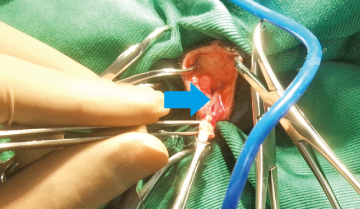

血尿を主訴に来院したプードルです。レントゲン検査と超音波検査で膀胱結石と診断しました。

矢印で示したのが結石です。

手術では膀胱を切開し、無事結石を全て摘出しました。

術後のレントゲン検査と超音波検査で結石が取り切れているのを確認。術後経過は良好で血尿も治まり退院しました。